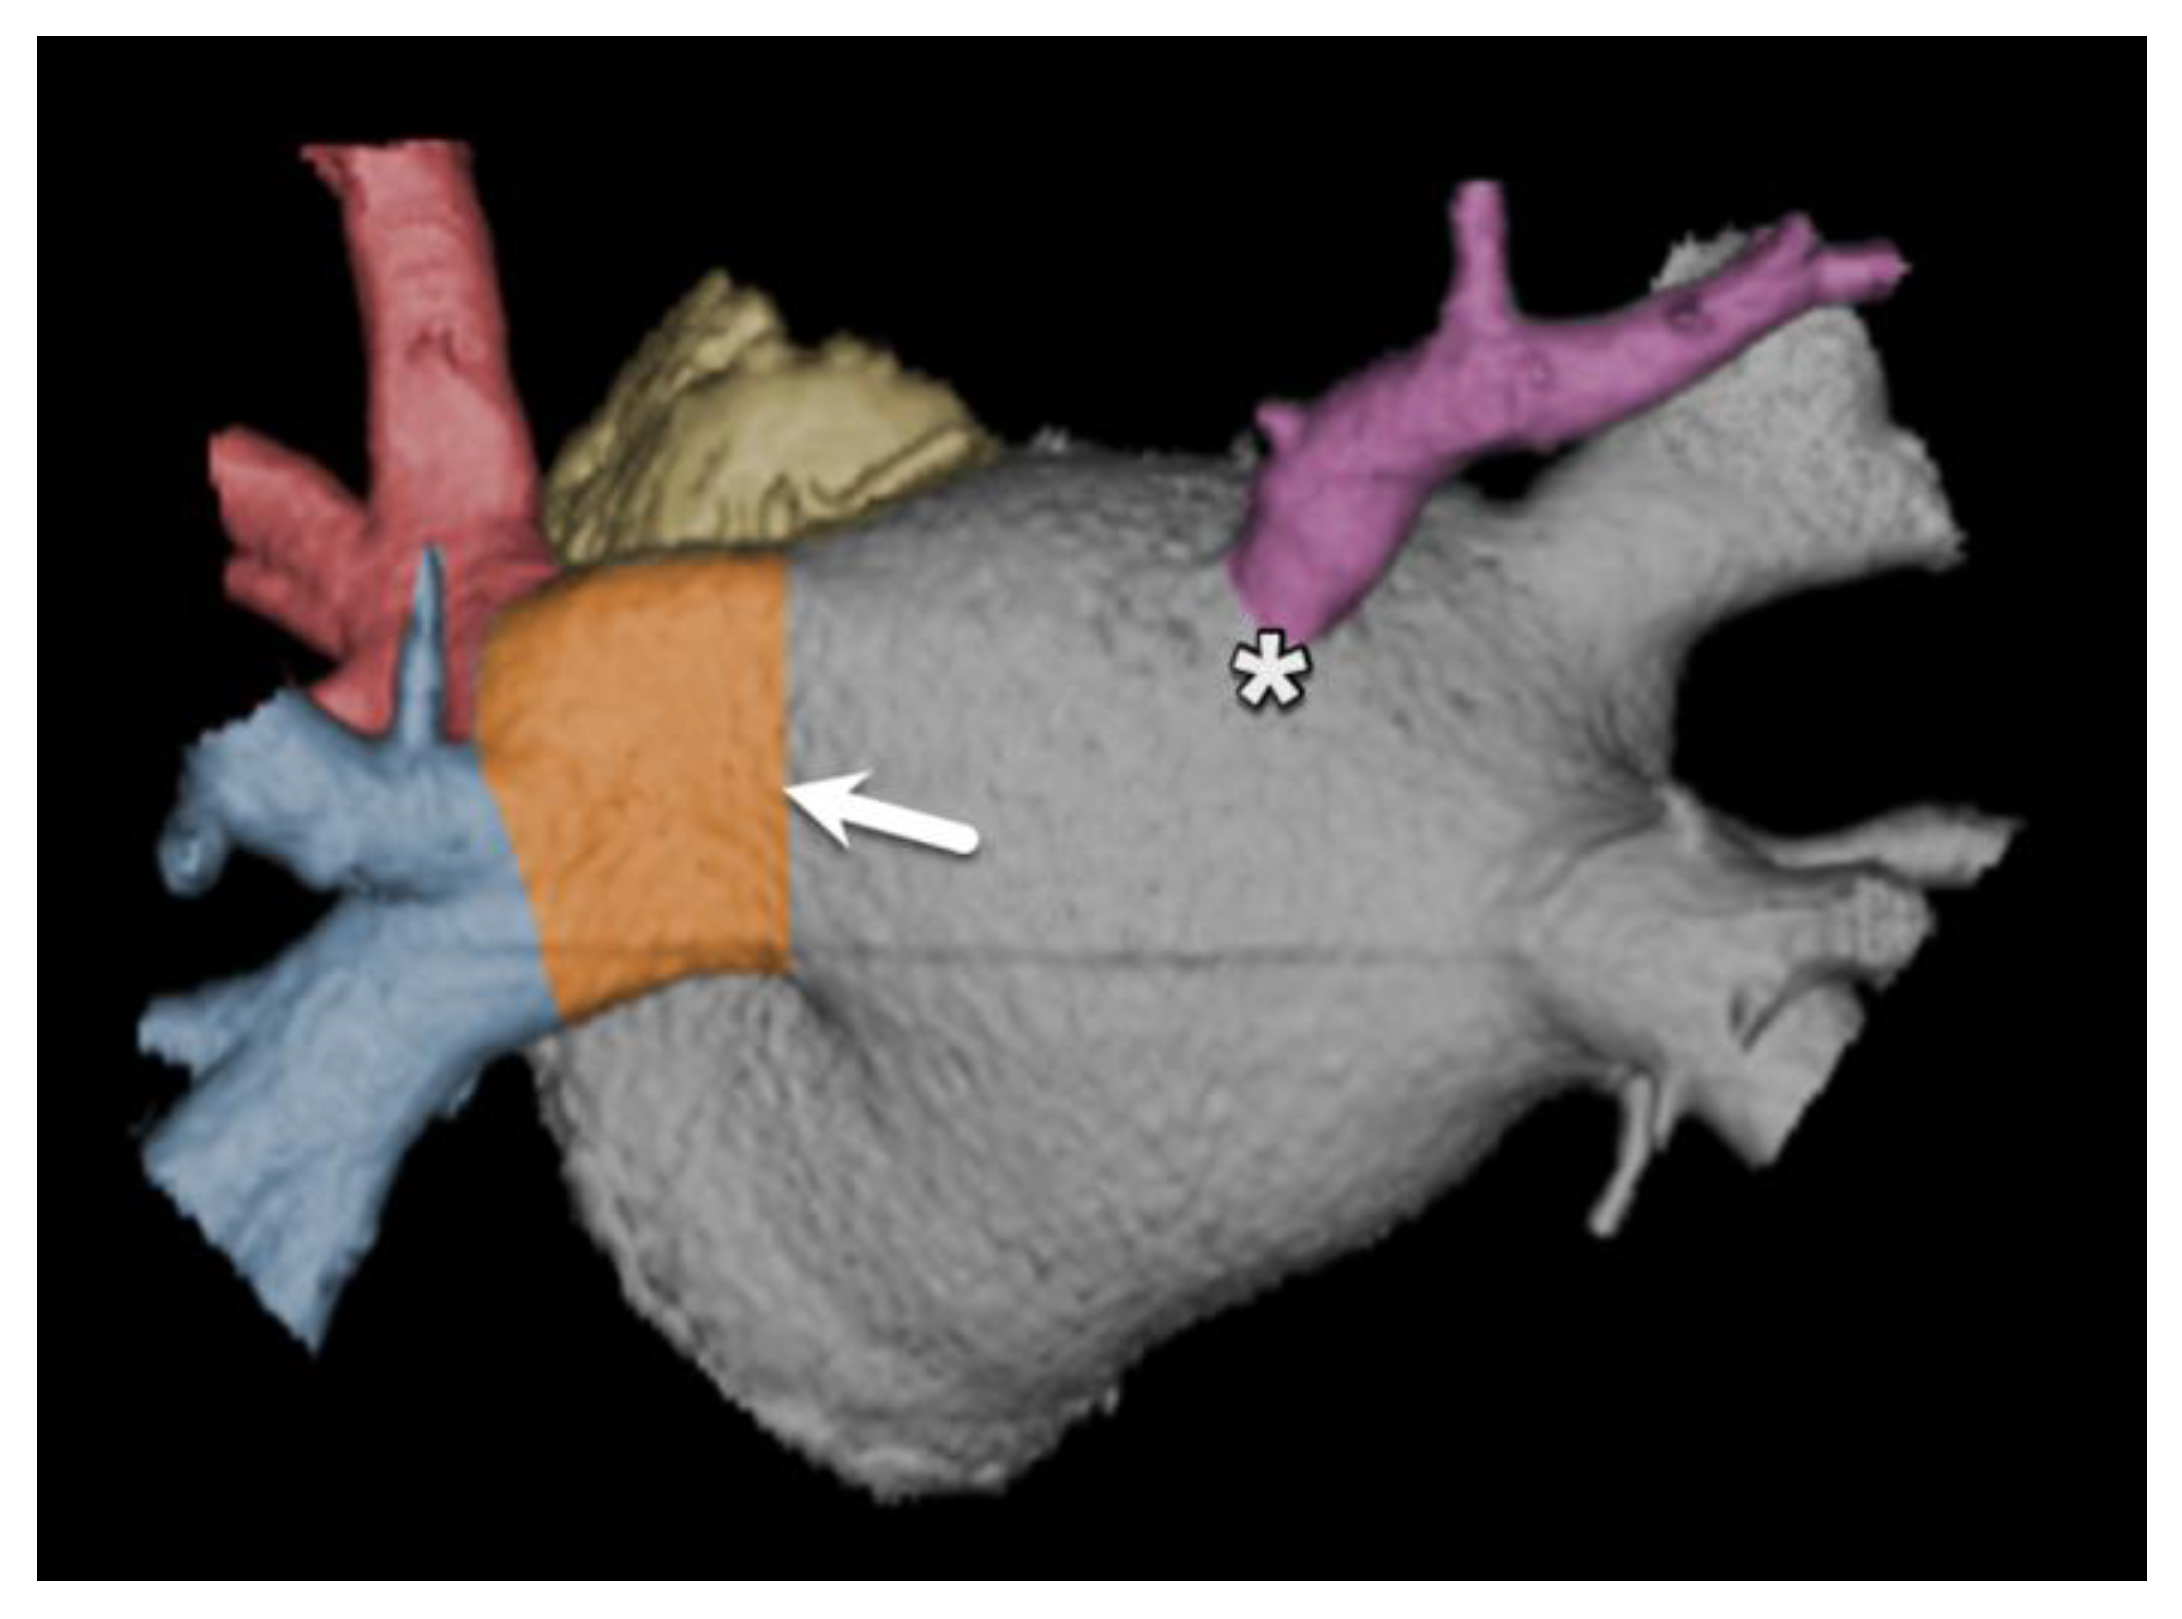

- Hell, M.M.; Emrich, T.; Kreidel, F.; Kreitner, K.-F.; Schoepf, U.J.; Münzel, T.; von Bardeleben, R.S. Computed tomography imaging needs for novel transcatheter tricuspid valve repair and replacement therapies. Eur. Heart J. Cardiovasc. Imaging 2020, 22, 601–610. [Google Scholar] [CrossRef] [PubMed]

- van Rosendael, P.J.; Kamperidis, V.; Kong, W.K.; van Rosendael, A.R.; van der Kley, F.; Ajmone Marsan, N.; Delgado, V.; Bax, J.J. Computed tomography for planning transcatheter tricuspid valve therapy. Eur. Heart J. 2017, 38, 665–674. [Google Scholar] [CrossRef] [PubMed]

- Naoum, C.; Blanke, P.; Cavalcante, J.L.; Leipsic, J. Cardiac Computed Tomography and Magnetic Resonance Imaging in the Evaluation of Mitral and Tricuspid Valve Disease. Circ. Cardiovasc. Imaging 2017, 10, e005331. [Google Scholar] [CrossRef]